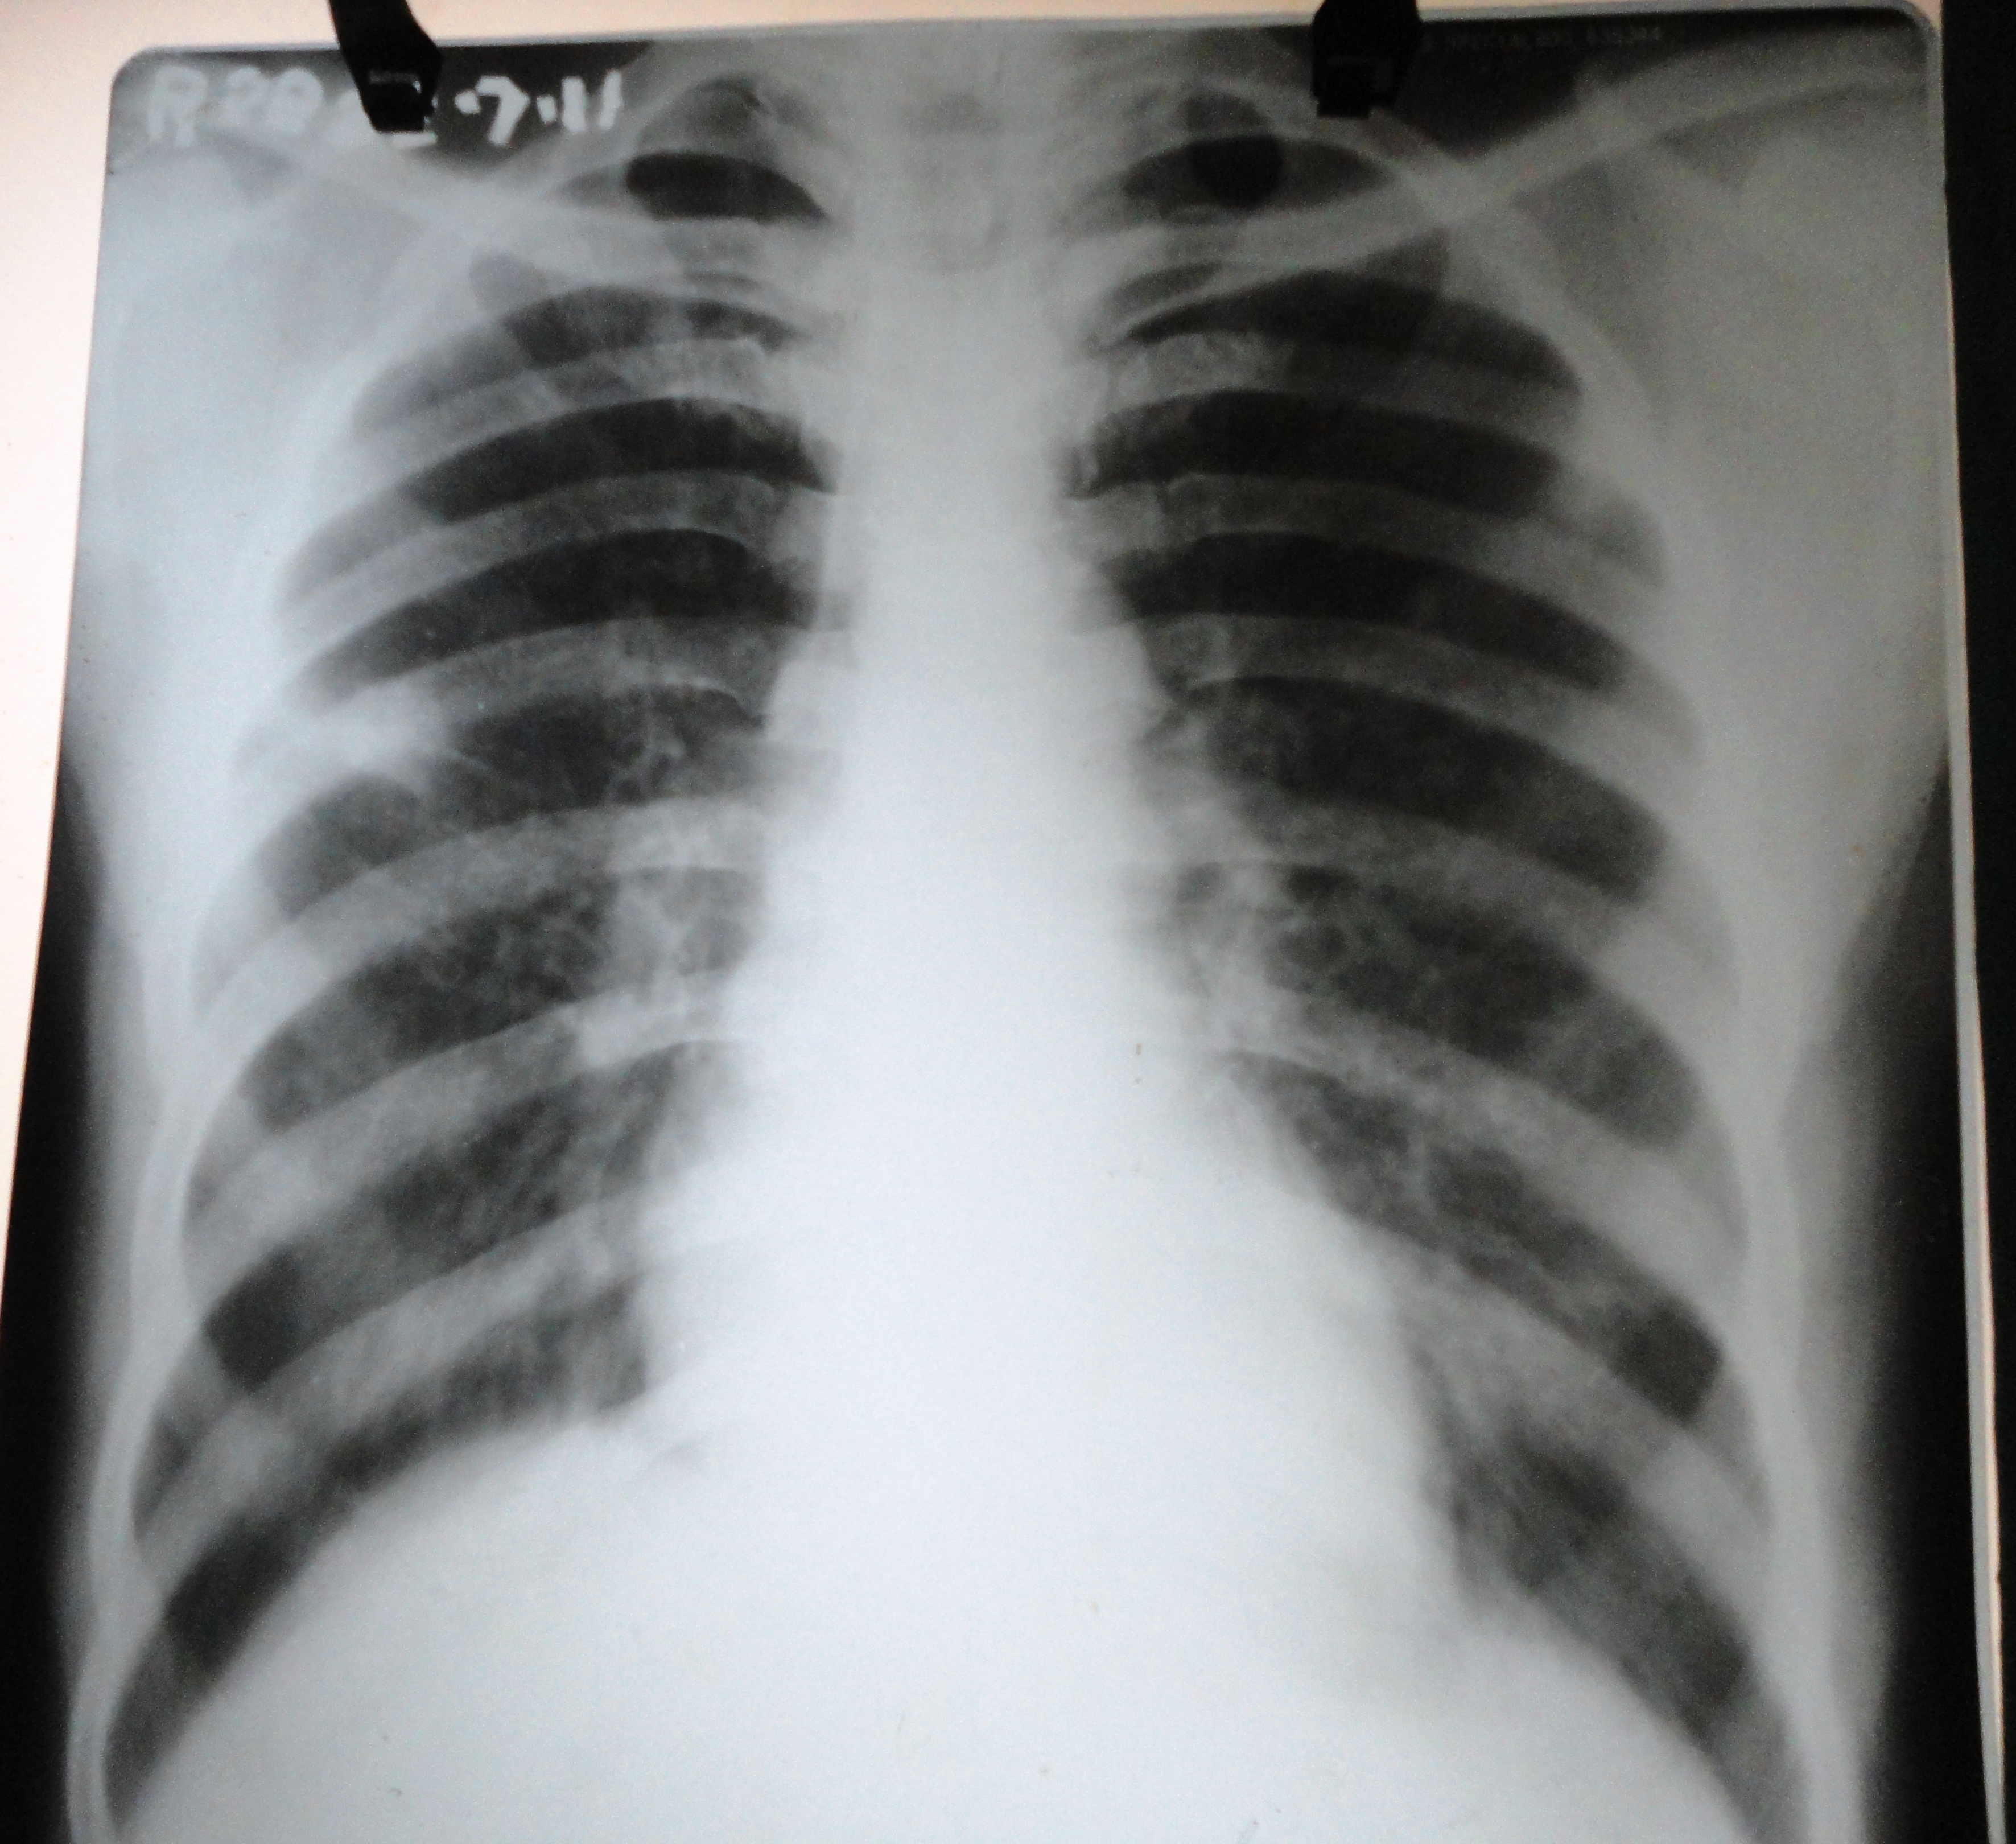

Adenocarcinoma and squamous cell carcinoma are the most frequently diagnosed histological subtype of bronchogenic carcinomas. Though metastatic lesions in lung are common in both the varieties, cavity formation has been documented only with squamous cell type. Here we are going to report a case of pulmonary adenocarcinoma with multiple nodular metastases in both lungs which show central necrosis mimicking cavities.